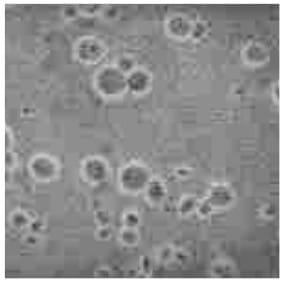

Virtually all HIV-1-associated cryptococcal infections are caused by Cryptococcus neoformans var

neoformans.

Cryptococcosis among patients with AIDS most commonly occurs as a subacute meningitis or meningoencephalitis with

fever, malaise and headache. Certain patients might present with encephalopathic symptoms (e.g., lethargy,

altered mentation, personality changes and memory loss).

Disseminated disease is a common manifestation, with or without concurrent meningitis. Approximately half of the

patients with disseminated disease have evidence of pulmonary rather than meningeal involvement. Symptoms and

signs of pulmonary infection include cough or dyspnea and abnormal chest radiographs. Skin lesions might be

observed.

Cryptococcal antigen is almost invariably detected in the CSF. If disseminated or other organ disease is

suspected in the absence of meningitis, a fungal blood culture is also diagnostically helpful. Detection of

cryptococcal antigen in serum might be useful in initial diagnosis.

Cryptococcus Smear

India ink preparation brings out the prominent translucent capsule of the organism.